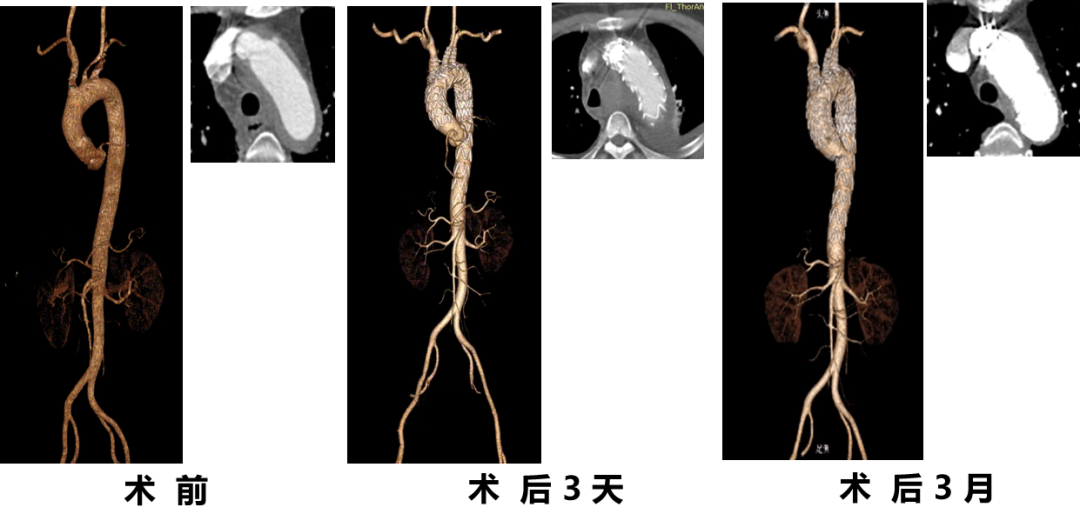

韩某,男,53岁,“查体发现主动脉弓部溃疡15天”入院,主动脉CTA提示:主动脉溃疡(弓部);2. 主动脉壁内血肿。患者高血压病史8年,最高210/130mmHg,无规律服药。

术前 CTA

术前

术后

手术用时115分钟